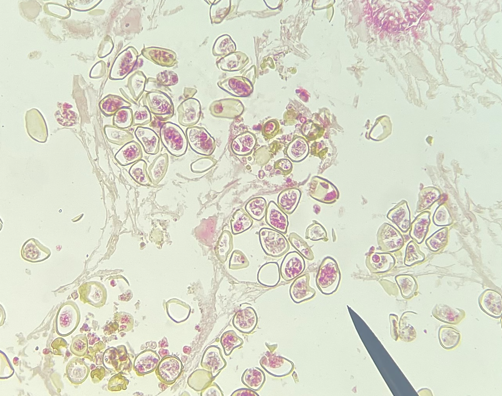

Schistosoma japonicum ova

Schistosoma spp. cercaria

40X magnification

40X magnification

Clonorchis sinensis